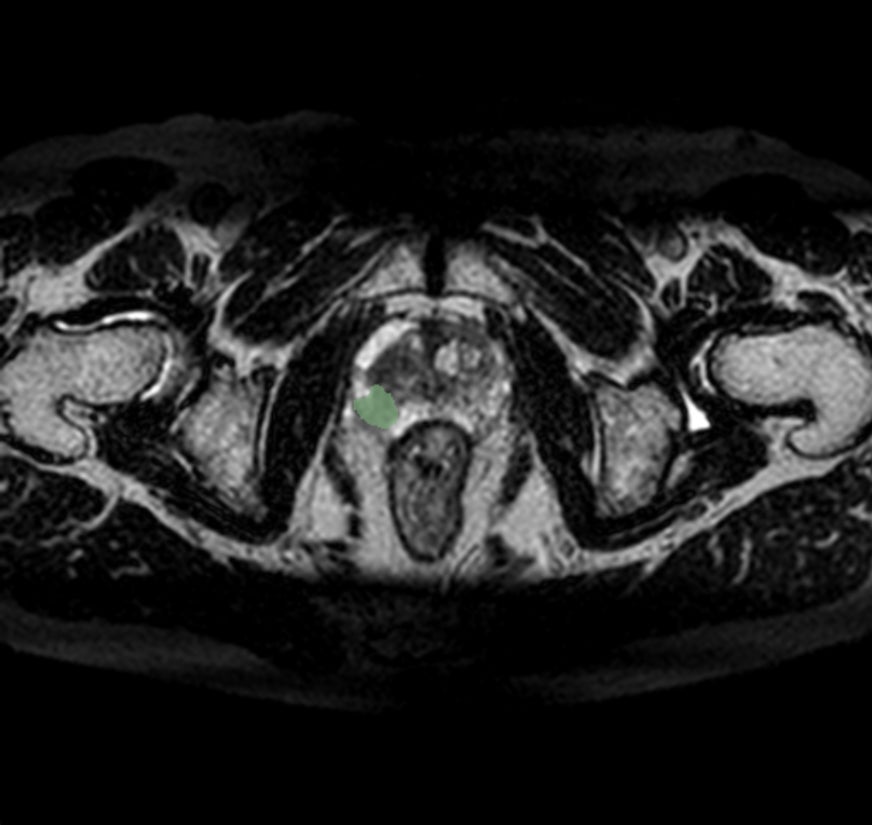

Callisto DataHub 2周年を記念し、専門医が作成した病変BBox付きの肺がん疑いX線データセット 50症例と、病変セグメンテーション付きの前立腺がんMRIデータセット(PI-RADS 4・5) 50症例を無料配布しています。前立腺がんMRIデータセットには、T1w, T2w, DWI, ADC, (あれば)DCEが含まれます。いずれも日本の医療施設由来で、所見文付き・商用利用可能なデータセットです。